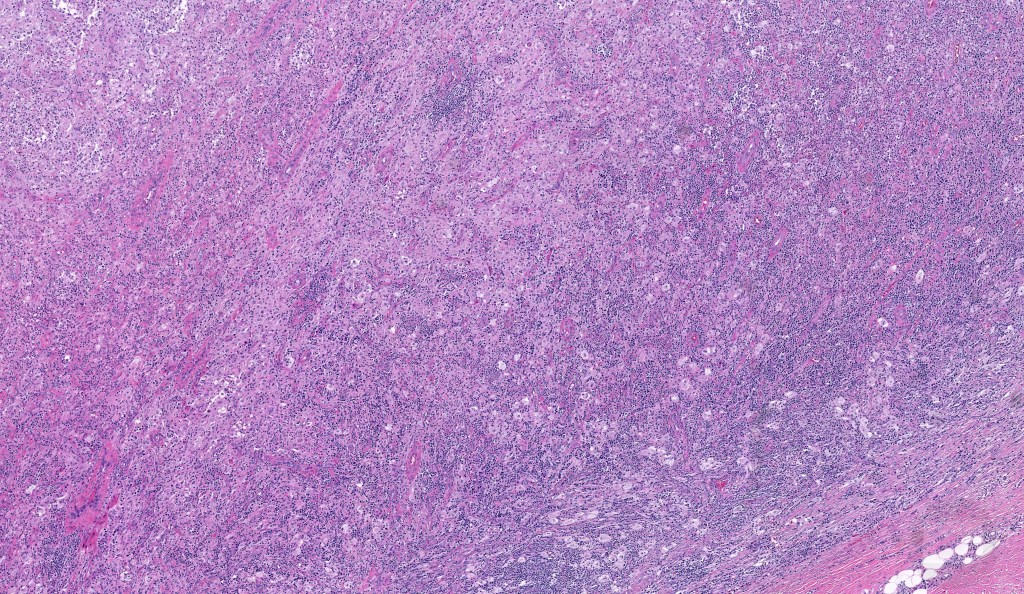

•Due to the admixture of pale histiocytes and lymphocytes, the scanning view is characteristic, and the diagnosis can be strongly suspected at this magnification

•Dense dermal nodular infiltrate sometimes extending into subcutaneous fat

•Fibrosis is occasionally conspicuous